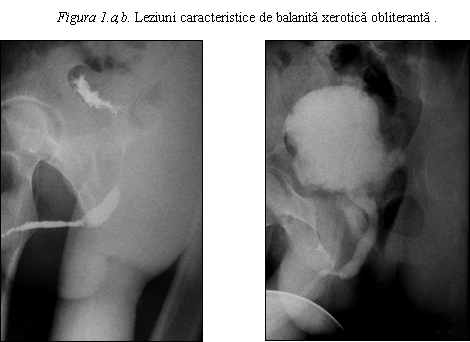

Balanita xerotic obliteranta (BXO) reprezinta o varietate cu localizare genitala a lichenului sclero-atrofic care se prezinta ca pete albicioase la nivelul preputului sau glandului, adesea interesand meatul si uneori fosa naviculara.

Leziunile pot fi multiple si pot avea aspect de mozaic.

Meatul apare albicios, indurat, edematos. Pot aparea eroziuni glandulare, fisuri si stenoza meatala.

Leziunea este mai des intalnita la barbatii necircumcisi, de varsta medie, dar totusi se poate intalni si la copii. Sunt descrise patru stadii ale bolii:

1. leziunea preputului care devine neretractil (fimoza)

2. leziunea preputului si glandului cu aderente intre ele

3. leziunea ce cuprinde preputul, glandul, meatul si uretra anterioara

4. leziuni asociate cu zone neoplazice - carcinom scuamos sau verucos.

Simptomele includ durere, disconfort local penian, prurit, erectii dureroase si obstructie urinara.

Histologic, se observa epiderm atrofic cu pierderea arhitectonicii normale, omogenizarea colagenului in treimea superioara a dermului, combinate cu zone de infiltrat limfocitar si histiocitar.

Leziunile seamana cu cele de lichen scleroatrofic descoperite in alte zone ale corpului.

Anumite studii asociaza balanita xerotic obliteranta cu carcinomul scuamocelular si cu dezvoltarea carcinomului la un interval mare dupa ce o leziune de balanita xerotic obliteranta a fost tratata.

Rara dar foarte dificil de tratat este afectarea uretrala intinsa ce necesita clasic excizia leziunilor si uretroplastie in doi timpi, dar rezultate bune au fost obtinute prin uretroplastie intr-un timp cu grefa de mucoasa bucala plasata dorsal.

a. b.

Figura 2.a,b. Strictura

intinsa a uretrei anterioare consecutiva BXO.